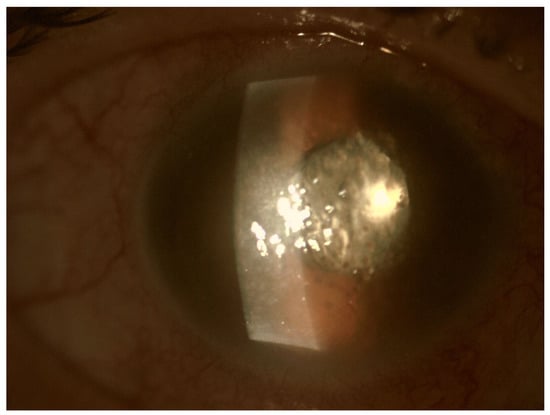

In EE, the transparency of optical media is often reduced. The cornea opacification and Descemet’s membrane folding are common. Tyndall can be found in the aqueous humor, often there is also hypopyon in the anterior chamber (Figure 3 and Figure 4). Inflammation and bacterial toxins are responsible for cataracts development and leakage of the lens proteins into the anterior chamber. In the case of posterior synechiae, the pupil does not respond to mydriatics (Figure 5).

Figure 5.

Posterior adhesions causing pupil irregularities. A slight hypopyon and ciliary congestion are also noteworthy.

Figure 2.

Pre-operative photo of the anterior segment of the eye in the patient presented in Figure 1. Attention is drawn to the widening of the conjunctival blood vessels, damage to the corneal epithelium and cell deposits on the endothelium. Due to the poor transparency of optical centers, the view into the fundus was significantly impaired.